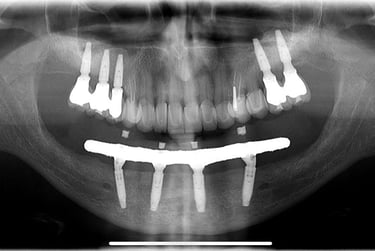

Comparação do Planejamento com o Resultado

Aspecto Radiográfico Final com Implantes e Coroas